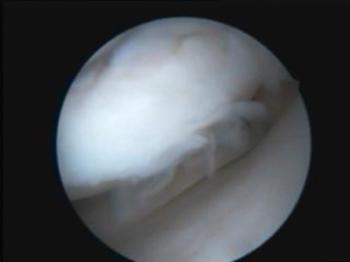

Ameliyat Öncesi 11100 OkunmaArtroskopik Cerrahi

Artroskopik Cerrahi - Yapım Aşamasında

Artroskopik Cerrahi 11866 OkunmaProtez Cerrahisi (Artroplasti)